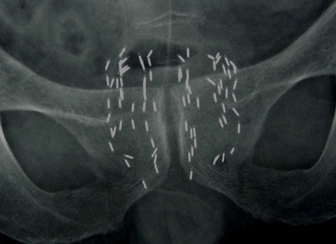

腹部X线平片明确粒子分布